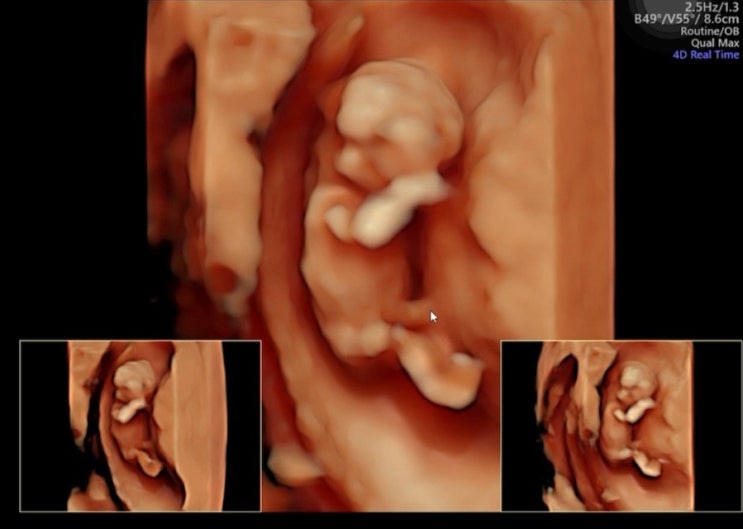

[9week] 분당여성제일병원 분만병원으로 전원하기 졸귀탱 젤리곰 아기 초음파

오늘 드디어 분만병원으로 전원을 하였다 기형아 검사 1,2차를 같은 병원에서 해야하는데 이왕이면 분만병...